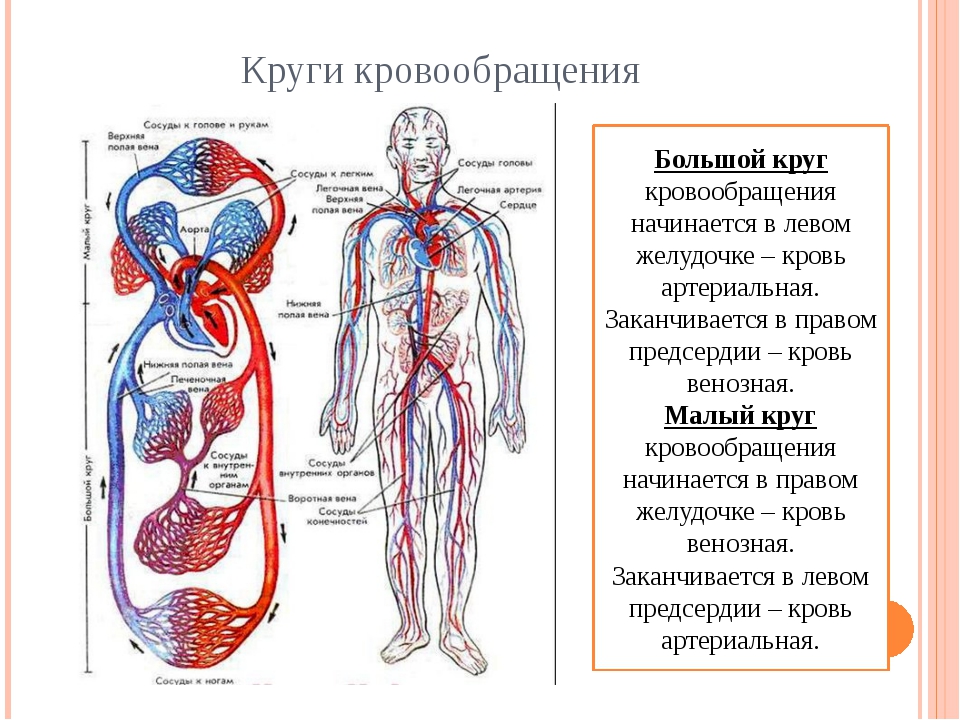

Кровеносная система человека: структура и функции